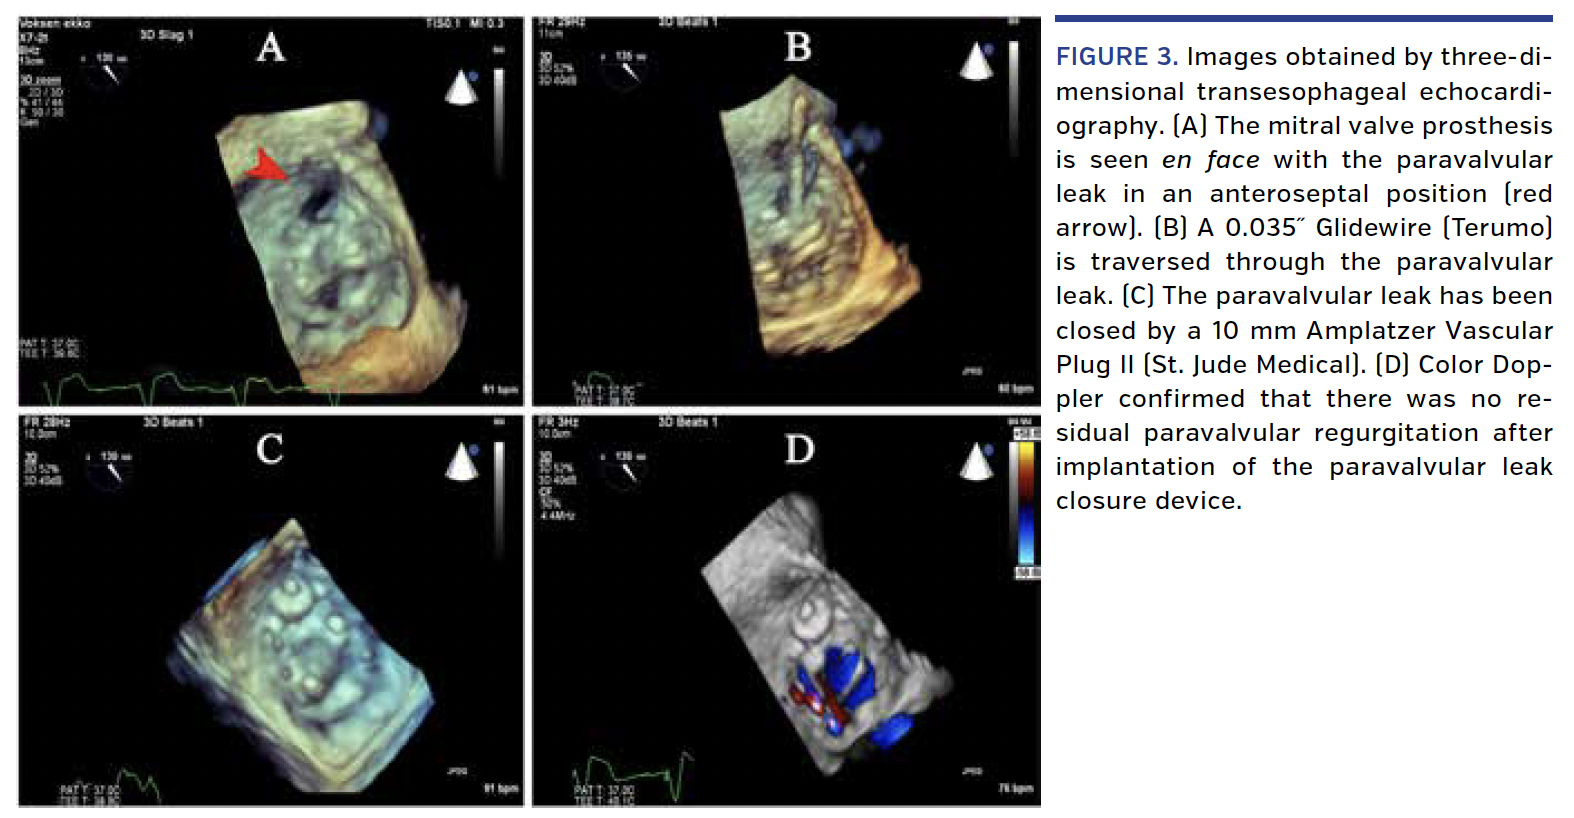

The PVL closure was performed under general anesthesia with three-dimensional transesophageal echocardiography (TEE) and a biplane Siemens Artis Zee angiographic system. An antegrade transseptal approach was used, with a puncture in the mid-portion of the atrial septum. The derived C-arm angulations were set giving a direct en face view and a perpendicular view of the mitral valve prosthesis. An 8.5 Fr steerable guiding sheath (Oscor) with a 6 Fr multipurpose coronary guiding catheter and a 0.035˝ Terumo Glidewire inside was placed in the left atrium and curved toward the PVL (Figures 2A and 2D). The PVL was easily crossed in less than 5 minutes (Figures 2B, 2E, 3B) due to the known spatial fluoroscopic anatomy and the exact site of the PVL relative to the prosthesis. TEE and intravascular ultrasound showed a maximum PVL channel diameter of 8 mm. A 10 mm Amplatzer Vascular Plug II (St. Jude Medical) was successfully expanded within the PVL (Figures 2C, 2F, 3C, 3D). Position and concealment of the leak were confirmed by TEE (Figures 3C and 3D) without interference between the closure device and mitral valve leaflets or left ventricular outflow tract flow. Stable device position was confirmed by fluoroscopy the day after the procedure. The patient had early and marked improvement in symptoms upon discharge.